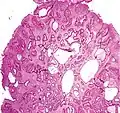

Juvenile Polyp Upper GI tract and colon Cystically dilated glands with expanded lamina propria Not inherently, may develop dysplasia

Juvenile polyposis syndrome, identical polyps in Cronkhite–Canada syndrome

Micrograph of a Peutz–Jeghers colonic polyp – a type of hamartomatous polyp. H&E stain.